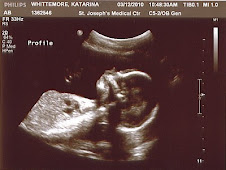

From there they took him back for his MRI and Heart Catheterization. The main purposes of the day was to get better pictures of the functionality of Eli's heart as well as the measurements of pressure and blood flow. Also the doctor wanted to make sure they had all the information that they needed going into his open heart surgery. Everything lasted about 4 hours.

We met with Dr Glatz afterwards who was really happy how everything looked and went. They showed us some incredible pictures and video of Eli's heart and blood flow. We feel really blessed with how great Eli is doing. His valves, heart function etc all looks great.  Eli has three holes in his heart. For normal hearts, holes are not good. For Eli his heart depends on it. Part of what they looked at during the cath was looking at the size of his top two holes (vsd). Dr Szwast and Dr Glatz both think that the size of the holes are good. That is great news. That means it looks like Eli will NOT need a pacemaker!!